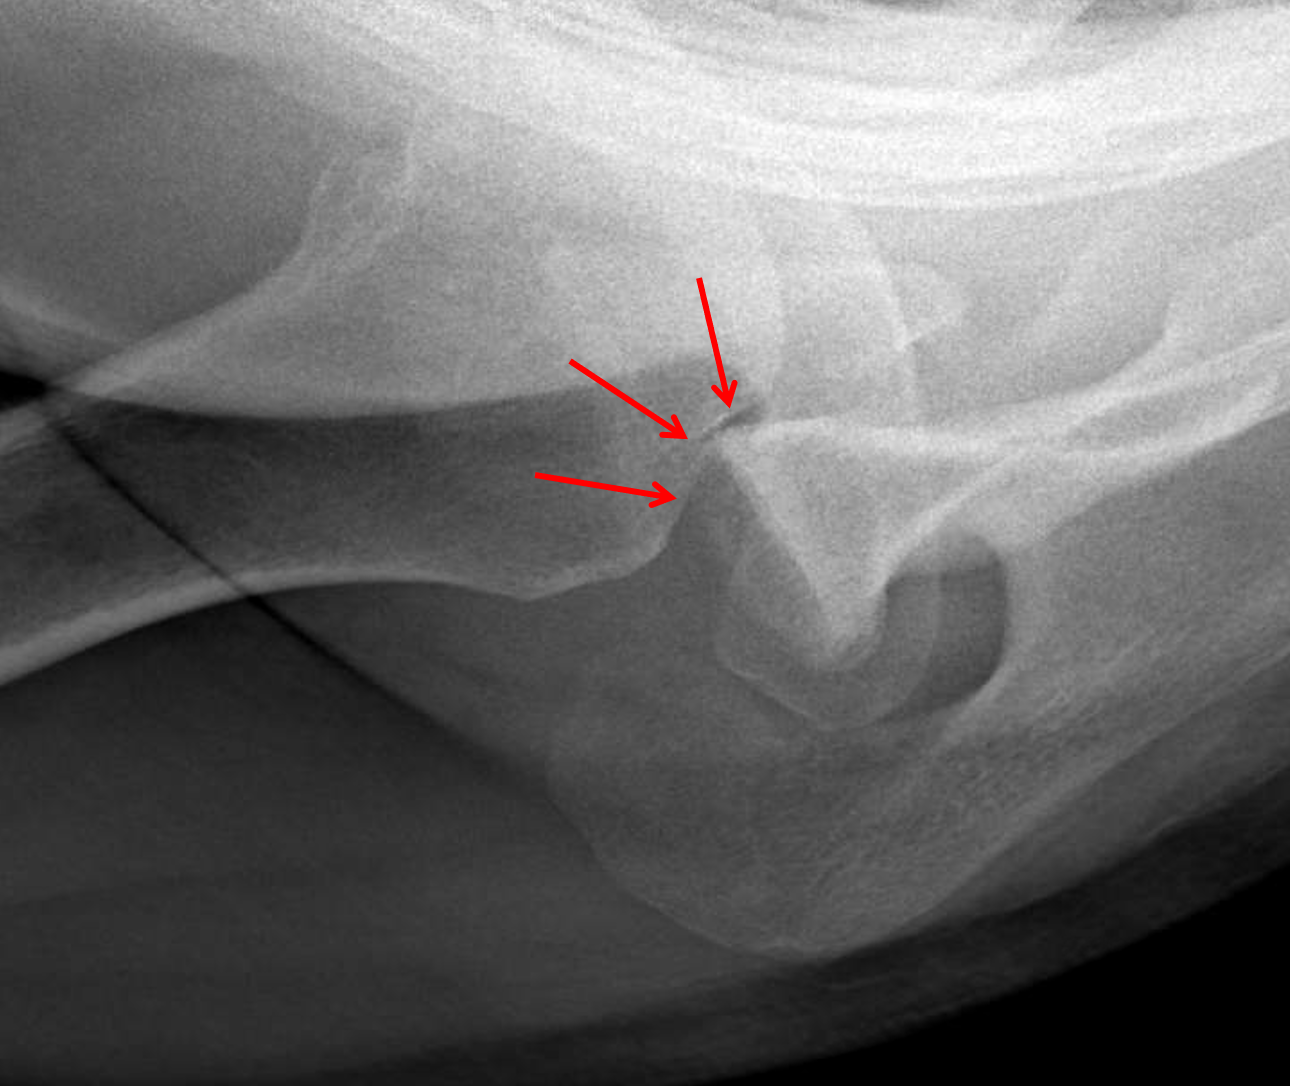

Film X ray shoulder show HillSachs lesion. Hill Sachs lesion is What Is A Hill Sachs Fracture The humeral head ‘collides’ with the anterior part of the glenoid, causing a lesion,. This injury causes bone damage to the ball of the shoulder joint. Is a compression fracture of the posterolateral humeral head due to its compression against. What Is A Hill Sachs Fracture.

Fig 14. Traumatic Anterior Dislocation xray of the same shoulder What Is A Hill Sachs Fracture Is a compression fracture of the posterolateral humeral head due to its compression against. This injury causes bone damage to the ball of the shoulder joint. The humeral head ‘collides’ with the anterior part of the glenoid, causing a lesion,. What Is A Hill Sachs Fracture.